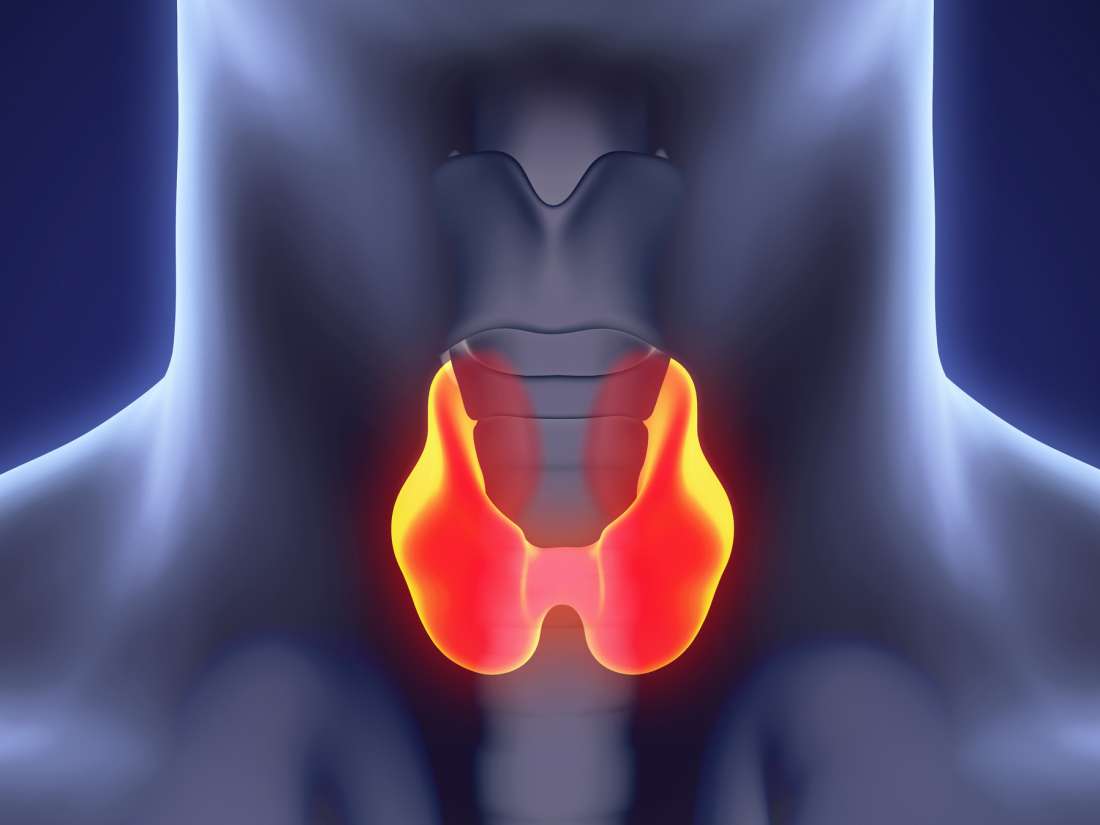

Staging System For Hpv Throat Cancer Head And Neck Cancer